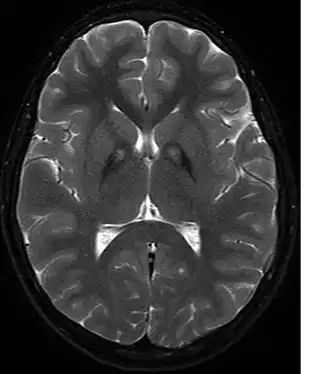

На МРТ изображены отложения железа в базальных ганглиях.

Необходимо биохимическое исключение болезни Вильсона-Коновалова, факультативно — исключение нейроакантоцитоза, прежде всего с помощью МРТ. В МРТ в Т2- взвешенных изображениях являются типичными — обусловленные отложением железа — гипоинтенсивные очаги в бледном шаре, с центральным очагом гиперинтенсивности — так называемые «глаза тигра». Этот симптом обнаруживается у всех больных с PANK2-мутациями. В генетическом обследовании могут обнаруживаться мутации в PANK2-гене. Тем не менее, уверенно можно говорить о диагнозе только после патологоанатомического исследования.